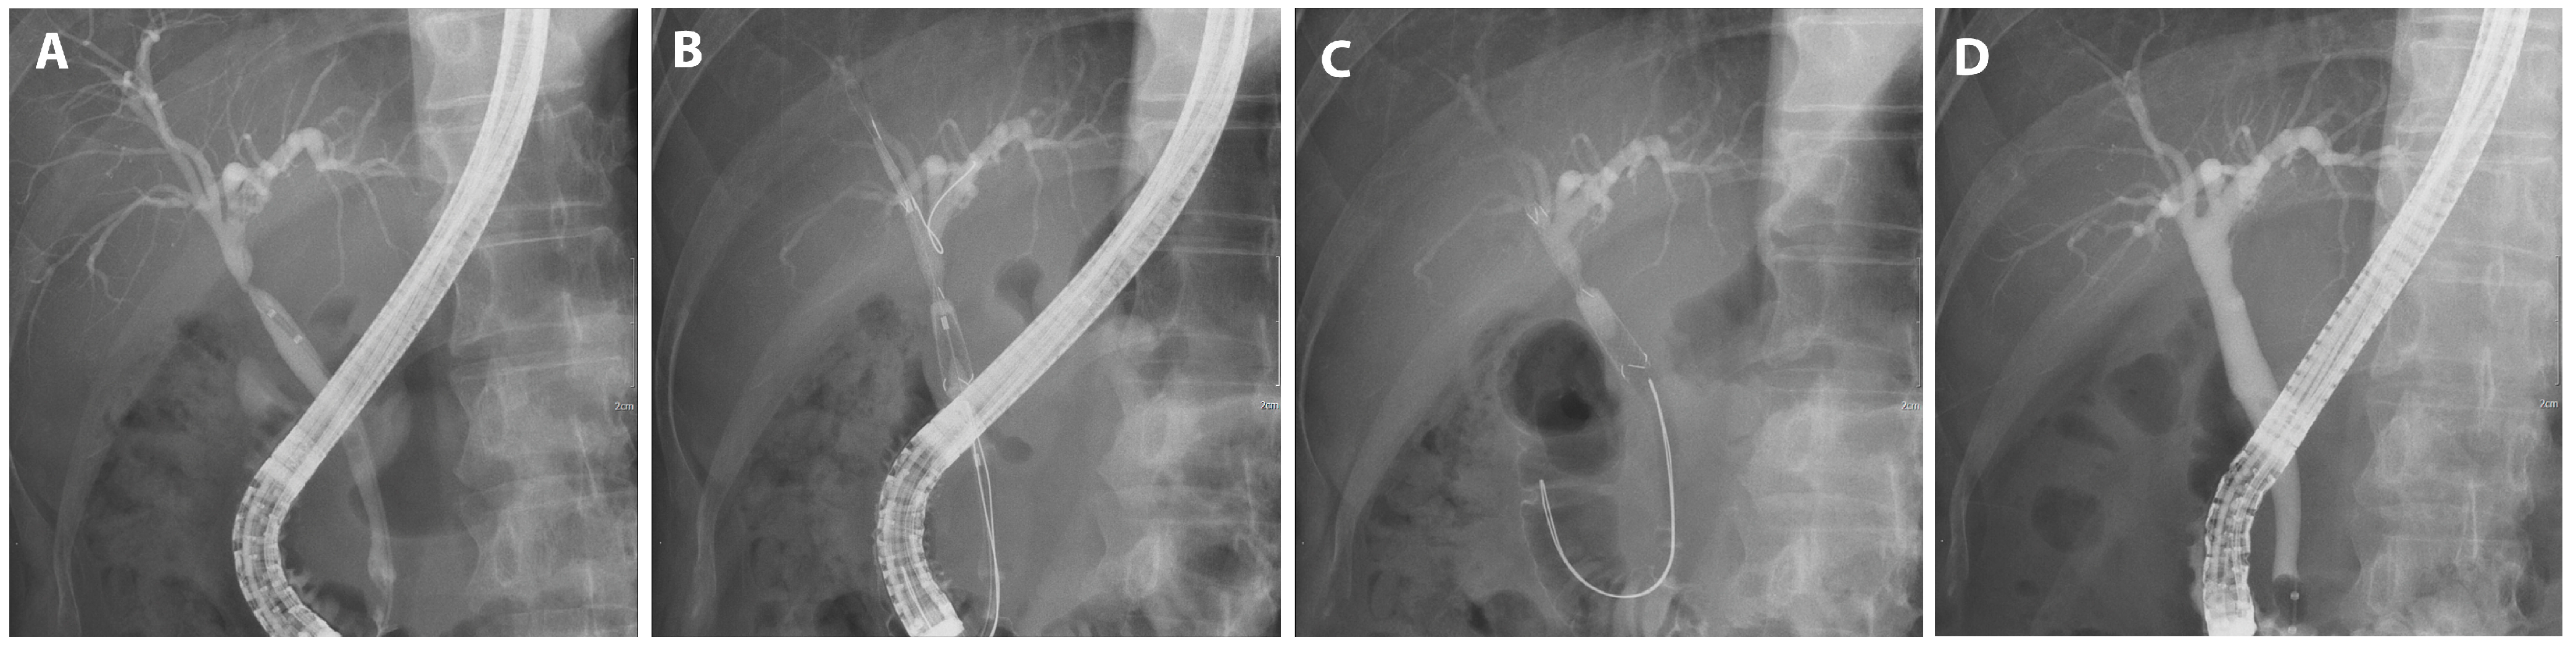

In instances where the stenosis persisted, the FCSEMS was reinserted. The stent was removed by pulling the retrieval string, which was visible in the duodenum, using endoscopic graspers (Figure 3E). After the procedure, patients were scheduled at 3 month intervals based on previous studies and considering the risk of stent occlusion and cholangitis [15], and were followed up every 1 month after stent placement to monitor for signs of stent occlusion. Cycles of FCSEMS deployment via ERCP were performed for up to 12 months or until complete resolution of BBS. The FCSEMS was positioned using the rendezvous technique when biliary cannulation was challenging or when a patient had previously undergone percutaneous transhepatic biliary drainage (PTBD). Moreover, in cases of BBS proximate to the hilar region, a precautionary measure was employed: a 7-Fr plastic stent (Zimmon, double pigtail type; Cook Medical) was pre-emptively placed prior to the FCSEMS insertion, especially in scenarios indicating potential blockage of adjacent biliary branches by the FCSEMS. In the subset of patients exhibiting multiple BBS presentations, as many as two FCSEMS were judiciously deployed to address each stenotic site.

Figure 3.

FCSEMS treatment of biliary anastomotic stricture after DDLT. A case of biliary anastomotic stricture that developed after DDLT for alcoholic cirrhosis and treated with FCSEMSs is presented. (A) A magnetic resonance cholangiopancreatograph was performed to visualize the shape and length of the stricture. A common bile duct stricture is shown. (B) A common bile duct stricture was observed on cholangiogram. (C) An FCSEMS (8 mm in diameter, 4 cm in length; KAFFES) stent was deployed so that the central radiopaque marker was centered in the stenosis. (D) The FCSEMS is shown at the stricture site, and the retrieval string is located at the duodenum (color figure). (E) After stent indwelling for 3 months, the FCSEMS was found to be completely self-inflating, and the FCSEMS is removed by grasping the retrieval string using grasping forceps (color panel). (F) After three months of FCSEMS, including one replacement, the stent was removed and the biliary anastomotic stricture resolved.

A case manifesting common bile duct (CBD) stricture subsequent to DDLT found resolution after a three-month FCSEMS application (Figure 3).